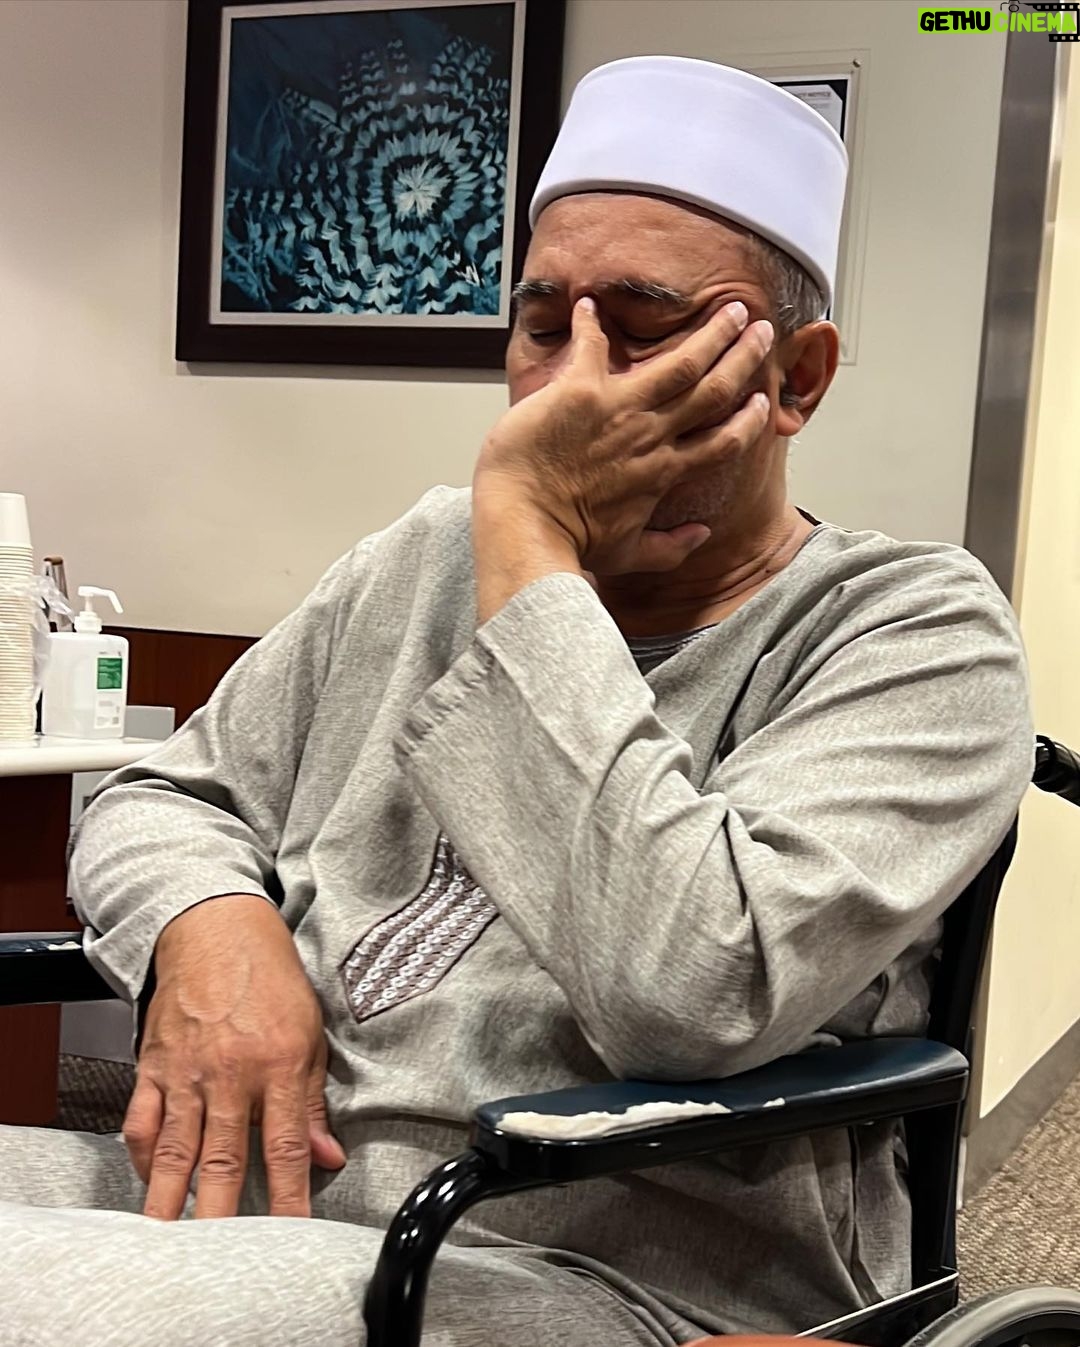

Caption : Kalau anyone you know jatuh kepala terhentak, luaran memang takde apa tapi dalaman maybe boleh jadi pendarahan perlahan. Sejurus dari terjatuh, bila check X-Ray dan CT scan it will tell you nothing, semua clear saja, but 2-3weeks later could turn into your biggest nightmare when the blood has flooded a big part of your brain. My dad realised something was wrong hampir sebulan lepas jatuh, when suddenly he couldn’t really move his right leg. Macam lagging. Sebab dia jatuh terhentak dahi kiri, bila anggota belah kanan yang terjejas, we knew it must be the brain. I picked him up and asked about his very very recent trip to Acheh, he said “Bila Daddy pergi Acheh?”. Ya Allah this very man, is my dad, someone who was very sharp and opinionated, tiba-tiba sangat blur dan slow, jawab sepatah-sepatah. So I spent the whole day uruskan dia, consulted two specialists and one neurosurgeon and when he is finally admitted that night to prepare him for his surgery the following day, he told the family “Daddy tadi drive sendiri datang sini”. My heart sank, I was frantic with worry — takutnya lagi lambat ni lagi banyak memori dia hilang. The brain surgery went well atas izin Allah, thank you to everyone involved. Doktor kata kalau lewat sikit je lagi memang boleh hilang keupayaan bercakap, keupayaan bernafas dan seterusnya koma, sebab otak dah compressed terlalu banyak darah. I jot this here as a reminder for all of us to always jangan tangguh-tangguh kalau hati dah tergerak. Daddy masih tak ingat I bawak dia pi hospital hari tu. Nasib baik kita selfie.Likes : 168141

Caption : Kalau anyone you know jatuh kepala terhentak, luaran memang takde apa tapi dalaman maybe boleh jadi pendarahan perlahan. Sejurus dari terjatuh, bila check X-Ray dan CT scan it will tell you nothing, semua clear saja, but 2-3weeks later could turn into your biggest nightmare when the blood has flooded a big part of your brain. My dad realised something was wrong hampir sebulan lepas jatuh, when suddenly he couldn’t really move his right leg. Macam lagging. Sebab dia jatuh terhentak dahi kiri, bila anggota belah kanan yang terjejas, we knew it must be the brain. I picked him up and asked about his very very recent trip to Acheh, he said “Bila Daddy pergi Acheh?”. Ya Allah this very man, is my dad, someone who was very sharp and opinionated, tiba-tiba sangat blur dan slow, jawab sepatah-sepatah. So I spent the whole day uruskan dia, consulted two specialists and one neurosurgeon and when he is finally admitted that night to prepare him for his surgery the following day, he told the family “Daddy tadi drive sendiri datang sini”. My heart sank, I was frantic with worry — takutnya lagi lambat ni lagi banyak memori dia hilang. The brain surgery went well atas izin Allah, thank you to everyone involved. Doktor kata kalau lewat sikit je lagi memang boleh hilang keupayaan bercakap, keupayaan bernafas dan seterusnya koma, sebab otak dah compressed terlalu banyak darah. I jot this here as a reminder for all of us to always jangan tangguh-tangguh kalau hati dah tergerak. Daddy masih tak ingat I bawak dia pi hospital hari tu. Nasib baik kita selfie.Likes : 168141

Caption : Kalau anyone you know jatuh kepala terhentak, luaran memang takde apa tapi dalaman maybe boleh jadi pendarahan perlahan. Sejurus dari terjatuh, bila check X-Ray dan CT scan it will tell you nothing, semua clear saja, but 2-3weeks later could turn into your biggest nightmare when the blood has flooded a big part of your brain. My dad realised something was wrong hampir sebulan lepas jatuh, when suddenly he couldn’t really move his right leg. Macam lagging. Sebab dia jatuh terhentak dahi kiri, bila anggota belah kanan yang terjejas, we knew it must be the brain. I picked him up and asked about his very very recent trip to Acheh, he said “Bila Daddy pergi Acheh?”. Ya Allah this very man, is my dad, someone who was very sharp and opinionated, tiba-tiba sangat blur dan slow, jawab sepatah-sepatah. So I spent the whole day uruskan dia, consulted two specialists and one neurosurgeon and when he is finally admitted that night to prepare him for his surgery the following day, he told the family “Daddy tadi drive sendiri datang sini”. My heart sank, I was frantic with worry — takutnya lagi lambat ni lagi banyak memori dia hilang. The brain surgery went well atas izin Allah, thank you to everyone involved. Doktor kata kalau lewat sikit je lagi memang boleh hilang keupayaan bercakap, keupayaan bernafas dan seterusnya koma, sebab otak dah compressed terlalu banyak darah. I jot this here as a reminder for all of us to always jangan tangguh-tangguh kalau hati dah tergerak. Daddy masih tak ingat I bawak dia pi hospital hari tu. Nasib baik kita selfie.Likes : 168141

Caption : Kalau anyone you know jatuh kepala terhentak, luaran memang takde apa tapi dalaman maybe boleh jadi pendarahan perlahan. Sejurus dari terjatuh, bila check X-Ray dan CT scan it will tell you nothing, semua clear saja, but 2-3weeks later could turn into your biggest nightmare when the blood has flooded a big part of your brain. My dad realised something was wrong hampir sebulan lepas jatuh, when suddenly he couldn’t really move his right leg. Macam lagging. Sebab dia jatuh terhentak dahi kiri, bila anggota belah kanan yang terjejas, we knew it must be the brain. I picked him up and asked about his very very recent trip to Acheh, he said “Bila Daddy pergi Acheh?”. Ya Allah this very man, is my dad, someone who was very sharp and opinionated, tiba-tiba sangat blur dan slow, jawab sepatah-sepatah. So I spent the whole day uruskan dia, consulted two specialists and one neurosurgeon and when he is finally admitted that night to prepare him for his surgery the following day, he told the family “Daddy tadi drive sendiri datang sini”. My heart sank, I was frantic with worry — takutnya lagi lambat ni lagi banyak memori dia hilang. The brain surgery went well atas izin Allah, thank you to everyone involved. Doktor kata kalau lewat sikit je lagi memang boleh hilang keupayaan bercakap, keupayaan bernafas dan seterusnya koma, sebab otak dah compressed terlalu banyak darah. I jot this here as a reminder for all of us to always jangan tangguh-tangguh kalau hati dah tergerak. Daddy masih tak ingat I bawak dia pi hospital hari tu. Nasib baik kita selfie.Likes : 168141

Caption : Kalau anyone you know jatuh kepala terhentak, luaran memang takde apa tapi dalaman maybe boleh jadi pendarahan perlahan. Sejurus dari terjatuh, bila check X-Ray dan CT scan it will tell you nothing, semua clear saja, but 2-3weeks later could turn into your biggest nightmare when the blood has flooded a big part of your brain. My dad realised something was wrong hampir sebulan lepas jatuh, when suddenly he couldn’t really move his right leg. Macam lagging. Sebab dia jatuh terhentak dahi kiri, bila anggota belah kanan yang terjejas, we knew it must be the brain. I picked him up and asked about his very very recent trip to Acheh, he said “Bila Daddy pergi Acheh?”. Ya Allah this very man, is my dad, someone who was very sharp and opinionated, tiba-tiba sangat blur dan slow, jawab sepatah-sepatah. So I spent the whole day uruskan dia, consulted two specialists and one neurosurgeon and when he is finally admitted that night to prepare him for his surgery the following day, he told the family “Daddy tadi drive sendiri datang sini”. My heart sank, I was frantic with worry — takutnya lagi lambat ni lagi banyak memori dia hilang. The brain surgery went well atas izin Allah, thank you to everyone involved. Doktor kata kalau lewat sikit je lagi memang boleh hilang keupayaan bercakap, keupayaan bernafas dan seterusnya koma, sebab otak dah compressed terlalu banyak darah. I jot this here as a reminder for all of us to always jangan tangguh-tangguh kalau hati dah tergerak. Daddy masih tak ingat I bawak dia pi hospital hari tu. Nasib baik kita selfie.Likes : 168141

Caption : Kalau anyone you know jatuh kepala terhentak, luaran memang takde apa tapi dalaman maybe boleh jadi pendarahan perlahan. Sejurus dari terjatuh, bila check X-Ray dan CT scan it will tell you nothing, semua clear saja, but 2-3weeks later could turn into your biggest nightmare when the blood has flooded a big part of your brain. My dad realised something was wrong hampir sebulan lepas jatuh, when suddenly he couldn’t really move his right leg. Macam lagging. Sebab dia jatuh terhentak dahi kiri, bila anggota belah kanan yang terjejas, we knew it must be the brain. I picked him up and asked about his very very recent trip to Acheh, he said “Bila Daddy pergi Acheh?”. Ya Allah this very man, is my dad, someone who was very sharp and opinionated, tiba-tiba sangat blur dan slow, jawab sepatah-sepatah. So I spent the whole day uruskan dia, consulted two specialists and one neurosurgeon and when he is finally admitted that night to prepare him for his surgery the following day, he told the family “Daddy tadi drive sendiri datang sini”. My heart sank, I was frantic with worry — takutnya lagi lambat ni lagi banyak memori dia hilang. The brain surgery went well atas izin Allah, thank you to everyone involved. Doktor kata kalau lewat sikit je lagi memang boleh hilang keupayaan bercakap, keupayaan bernafas dan seterusnya koma, sebab otak dah compressed terlalu banyak darah. I jot this here as a reminder for all of us to always jangan tangguh-tangguh kalau hati dah tergerak. Daddy masih tak ingat I bawak dia pi hospital hari tu. Nasib baik kita selfie.Likes : 168141

Caption : Kalau anyone you know jatuh kepala terhentak, luaran memang takde apa tapi dalaman maybe boleh jadi pendarahan perlahan. Sejurus dari terjatuh, bila check X-Ray dan CT scan it will tell you nothing, semua clear saja, but 2-3weeks later could turn into your biggest nightmare when the blood has flooded a big part of your brain. My dad realised something was wrong hampir sebulan lepas jatuh, when suddenly he couldn’t really move his right leg. Macam lagging. Sebab dia jatuh terhentak dahi kiri, bila anggota belah kanan yang terjejas, we knew it must be the brain. I picked him up and asked about his very very recent trip to Acheh, he said “Bila Daddy pergi Acheh?”. Ya Allah this very man, is my dad, someone who was very sharp and opinionated, tiba-tiba sangat blur dan slow, jawab sepatah-sepatah. So I spent the whole day uruskan dia, consulted two specialists and one neurosurgeon and when he is finally admitted that night to prepare him for his surgery the following day, he told the family “Daddy tadi drive sendiri datang sini”. My heart sank, I was frantic with worry — takutnya lagi lambat ni lagi banyak memori dia hilang. The brain surgery went well atas izin Allah, thank you to everyone involved. Doktor kata kalau lewat sikit je lagi memang boleh hilang keupayaan bercakap, keupayaan bernafas dan seterusnya koma, sebab otak dah compressed terlalu banyak darah. I jot this here as a reminder for all of us to always jangan tangguh-tangguh kalau hati dah tergerak. Daddy masih tak ingat I bawak dia pi hospital hari tu. Nasib baik kita selfie.Likes : 168141

Caption : Kalau anyone you know jatuh kepala terhentak, luaran memang takde apa tapi dalaman maybe boleh jadi pendarahan perlahan. Sejurus dari terjatuh, bila check X-Ray dan CT scan it will tell you nothing, semua clear saja, but 2-3weeks later could turn into your biggest nightmare when the blood has flooded a big part of your brain. My dad realised something was wrong hampir sebulan lepas jatuh, when suddenly he couldn’t really move his right leg. Macam lagging. Sebab dia jatuh terhentak dahi kiri, bila anggota belah kanan yang terjejas, we knew it must be the brain. I picked him up and asked about his very very recent trip to Acheh, he said “Bila Daddy pergi Acheh?”. Ya Allah this very man, is my dad, someone who was very sharp and opinionated, tiba-tiba sangat blur dan slow, jawab sepatah-sepatah. So I spent the whole day uruskan dia, consulted two specialists and one neurosurgeon and when he is finally admitted that night to prepare him for his surgery the following day, he told the family “Daddy tadi drive sendiri datang sini”. My heart sank, I was frantic with worry — takutnya lagi lambat ni lagi banyak memori dia hilang. The brain surgery went well atas izin Allah, thank you to everyone involved. Doktor kata kalau lewat sikit je lagi memang boleh hilang keupayaan bercakap, keupayaan bernafas dan seterusnya koma, sebab otak dah compressed terlalu banyak darah. I jot this here as a reminder for all of us to always jangan tangguh-tangguh kalau hati dah tergerak. Daddy masih tak ingat I bawak dia pi hospital hari tu. Nasib baik kita selfie.Likes : 168141

Caption : Kalau anyone you know jatuh kepala terhentak, luaran memang takde apa tapi dalaman maybe boleh jadi pendarahan perlahan. Sejurus dari terjatuh, bila check X-Ray dan CT scan it will tell you nothing, semua clear saja, but 2-3weeks later could turn into your biggest nightmare when the blood has flooded a big part of your brain. My dad realised something was wrong hampir sebulan lepas jatuh, when suddenly he couldn’t really move his right leg. Macam lagging. Sebab dia jatuh terhentak dahi kiri, bila anggota belah kanan yang terjejas, we knew it must be the brain. I picked him up and asked about his very very recent trip to Acheh, he said “Bila Daddy pergi Acheh?”. Ya Allah this very man, is my dad, someone who was very sharp and opinionated, tiba-tiba sangat blur dan slow, jawab sepatah-sepatah. So I spent the whole day uruskan dia, consulted two specialists and one neurosurgeon and when he is finally admitted that night to prepare him for his surgery the following day, he told the family “Daddy tadi drive sendiri datang sini”. My heart sank, I was frantic with worry — takutnya lagi lambat ni lagi banyak memori dia hilang. The brain surgery went well atas izin Allah, thank you to everyone involved. Doktor kata kalau lewat sikit je lagi memang boleh hilang keupayaan bercakap, keupayaan bernafas dan seterusnya koma, sebab otak dah compressed terlalu banyak darah. I jot this here as a reminder for all of us to always jangan tangguh-tangguh kalau hati dah tergerak. Daddy masih tak ingat I bawak dia pi hospital hari tu. Nasib baik kita selfie.Likes : 168141

Caption : Kalau anyone you know jatuh kepala terhentak, luaran memang takde apa tapi dalaman maybe boleh jadi pendarahan perlahan. Sejurus dari terjatuh, bila check X-Ray dan CT scan it will tell you nothing, semua clear saja, but 2-3weeks later could turn into your biggest nightmare when the blood has flooded a big part of your brain. My dad realised something was wrong hampir sebulan lepas jatuh, when suddenly he couldn’t really move his right leg. Macam lagging. Sebab dia jatuh terhentak dahi kiri, bila anggota belah kanan yang terjejas, we knew it must be the brain. I picked him up and asked about his very very recent trip to Acheh, he said “Bila Daddy pergi Acheh?”. Ya Allah this very man, is my dad, someone who was very sharp and opinionated, tiba-tiba sangat blur dan slow, jawab sepatah-sepatah. So I spent the whole day uruskan dia, consulted two specialists and one neurosurgeon and when he is finally admitted that night to prepare him for his surgery the following day, he told the family “Daddy tadi drive sendiri datang sini”. My heart sank, I was frantic with worry — takutnya lagi lambat ni lagi banyak memori dia hilang. The brain surgery went well atas izin Allah, thank you to everyone involved. Doktor kata kalau lewat sikit je lagi memang boleh hilang keupayaan bercakap, keupayaan bernafas dan seterusnya koma, sebab otak dah compressed terlalu banyak darah. I jot this here as a reminder for all of us to always jangan tangguh-tangguh kalau hati dah tergerak. Daddy masih tak ingat I bawak dia pi hospital hari tu. Nasib baik kita selfie.Likes : 168141